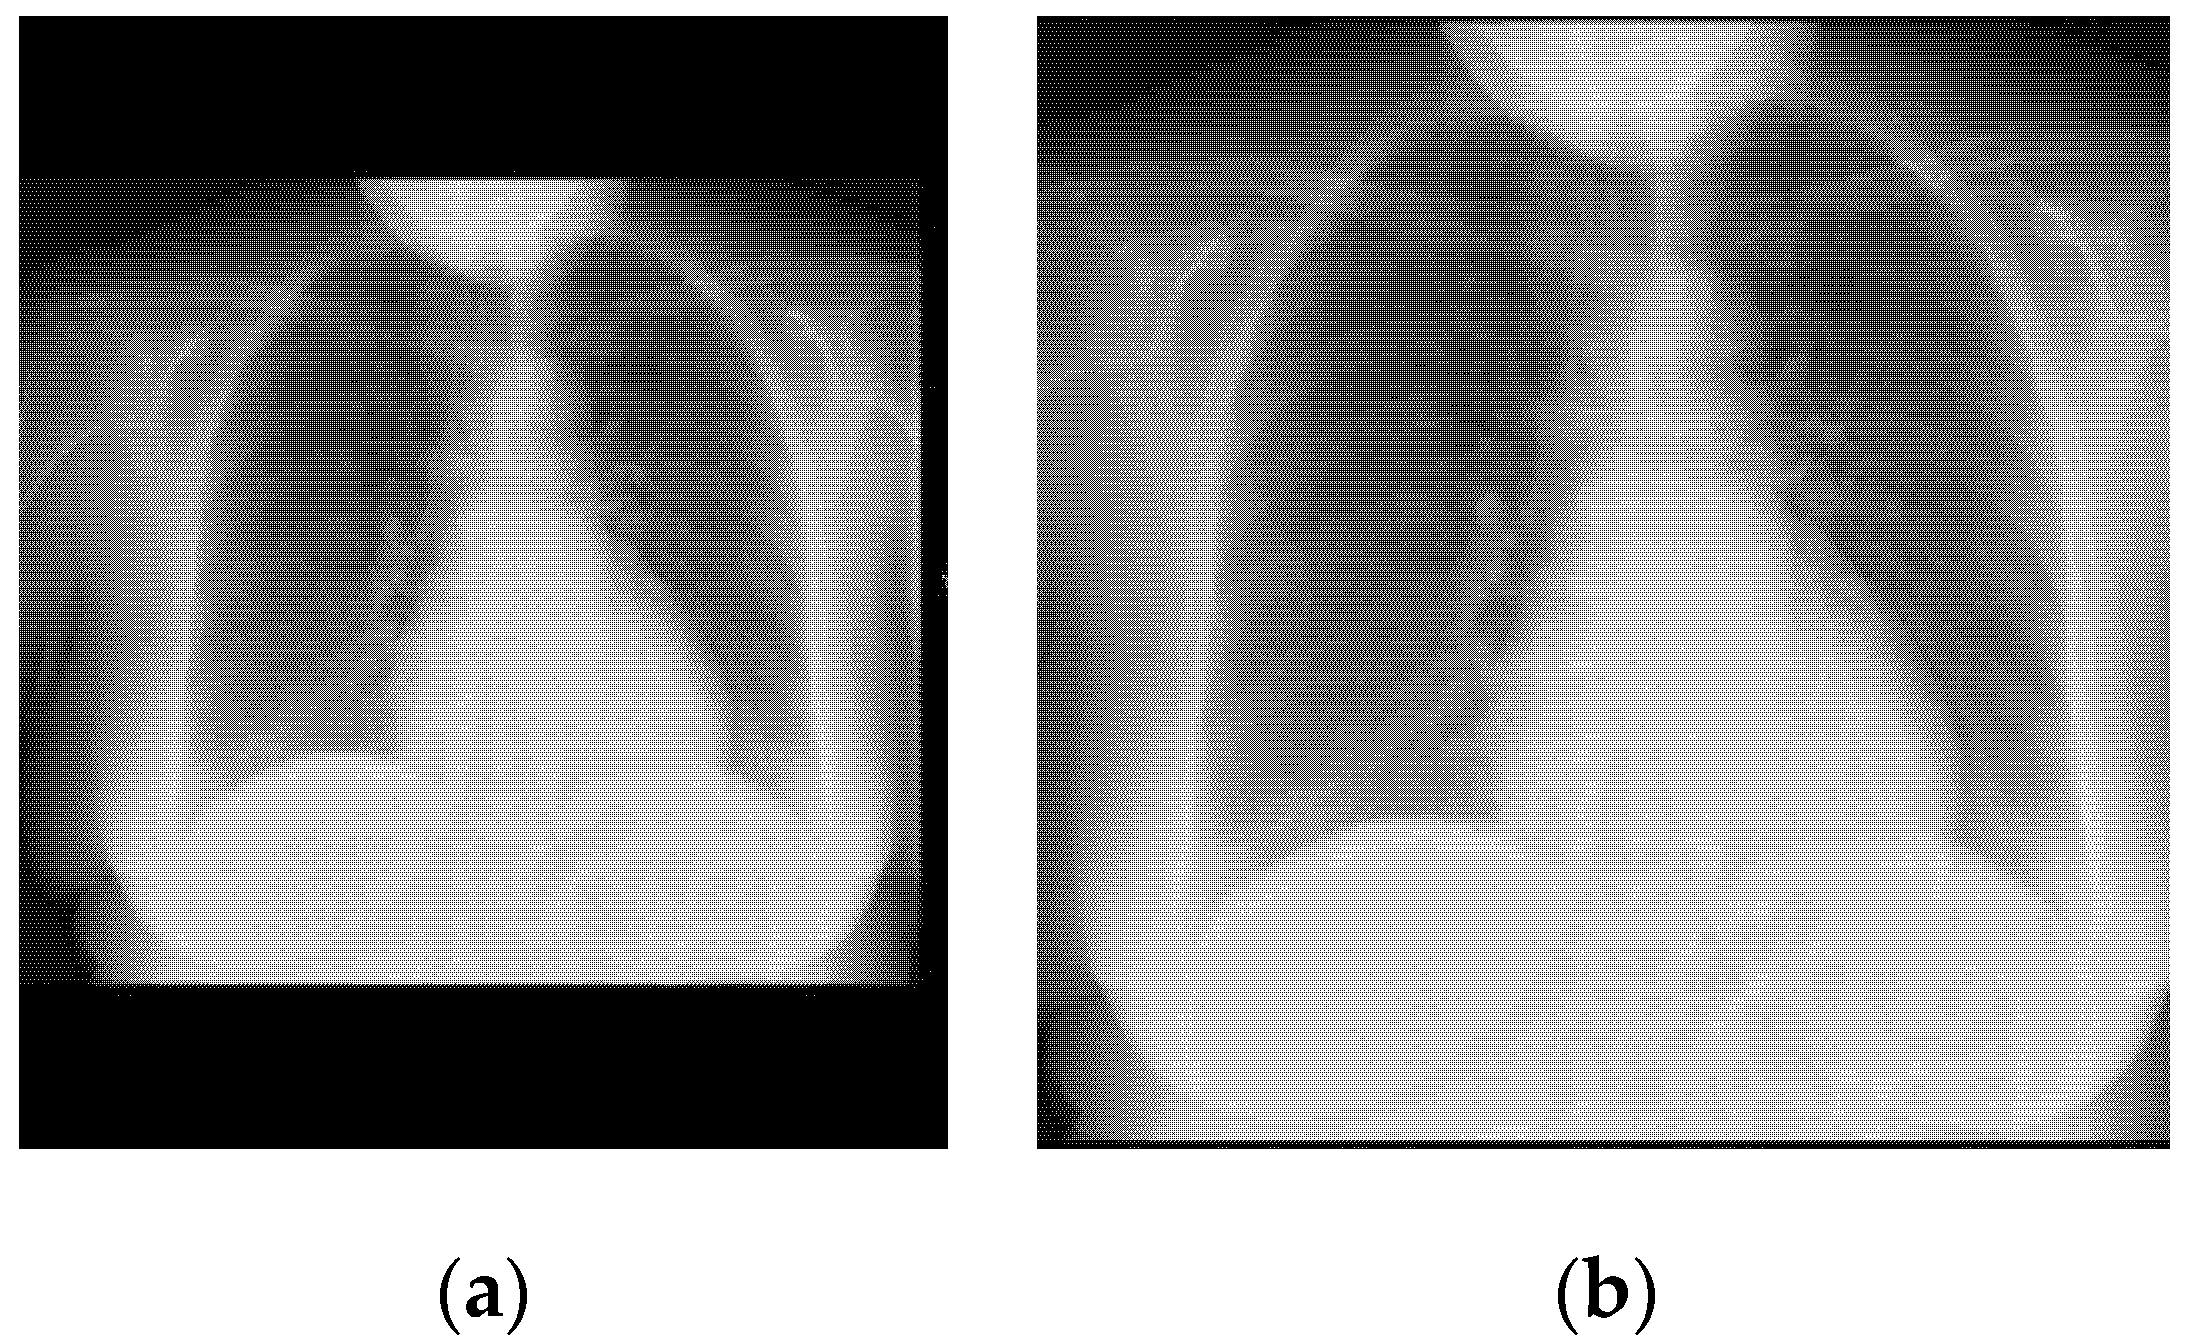

4.1. Image Preprocessing

- If some black band appears at the edges, they are removed.

- The size of the image is transformed until the smallest border measures 299 pixels.

- Extract the central region of 299 × 299 pixels.